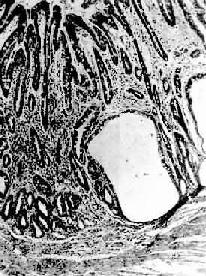

镜下,病变区腺上皮萎缩,腺体变小并可有囊性扩张,常出现上皮化生(假幽门腺化生及肠上皮化生)。在粘膜固有层有不同程度的淋巴细胞和浆细胞浸润。在胃体和胃底部病变区,主要呈现壁细胞消失,其次是主细胞消失和粘液分泌细胞化生。后者称为幽门腺或假幽门腺化生。电镜观察,壁细胞除数量减少外,可见细胞内自噬泡增多,内质网扩张,高尔基器减少,线粒体肿胀,表面微绒毛消失。内质网、高尔基器和微绒毛是壁细胞的功能部分,其减少或消失反映了细胞泌酸功能的低下或消失。在幽门窦病变区,主要改变为幽门腺呈不同程度的萎缩、消失(图10-3)并常有肠上皮化生。胃粘膜表层上皮细胞生长,可形成绒毛样突起,增生的上皮中出现分泌粘液的杯状细胞(图10-4)、具有刷状缘的吸收上皮细胞和Paneth细胞时其形态结构与小肠粘膜相似,故称为肠上皮化生。现知肠上皮化生的胃粘膜易诱发胃,多为息肉样腺

慢性萎缩性胃炎

图10-3 慢性萎缩性胃炎

幽门腺大部分萎缩消失,胃小凹延长,有潴留性小囊形成,腺上皮中杂有不少杯状细胞(肠上皮化生),固有膜内有不少慢性炎性细胞浸润(Ⅱ74-4950)